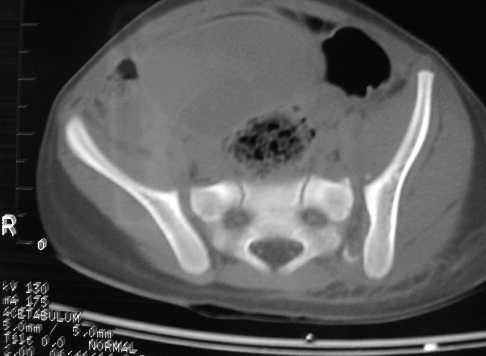

A 3 y-old girl, injured by after a traffic accident, no other skeletal and organ injuries. She was in skeletal traction now and initial, after skeletal traction AP views and CT scans of the pelvis were attached.